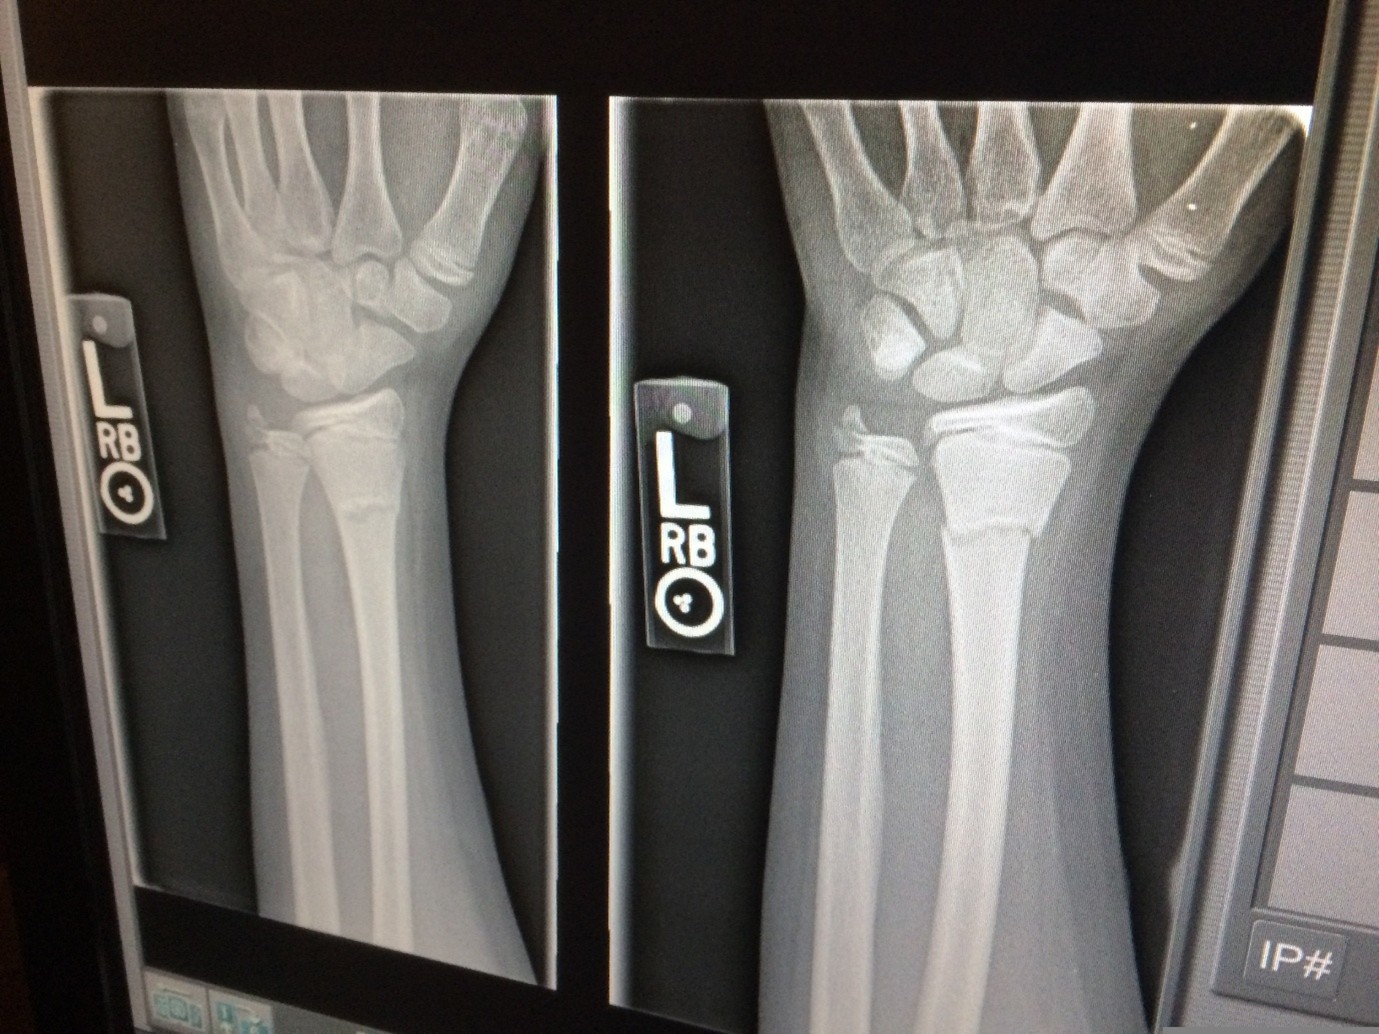

- zlomi ob manjših obremenitvah

Diagnoza se običajno postavi na podlagi merjenja kostne gostote (DXA), ki pokaže, kako močne so vaše kosti.

Osteoporoza je kronična, pogosto neopazna bolezen, pri kateri se zmanjšuje kostna gostota, kar vodi v večjo krhkost kosti in povečano tveganje za zlome – pogosto že ob manjših obremenitvah.